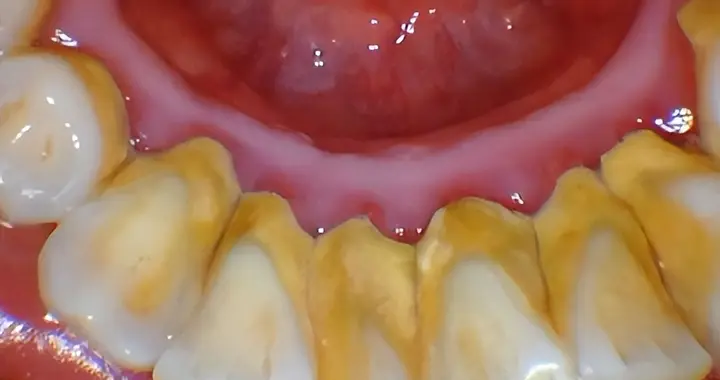

牙齿为什么黏糊糊的?原来因为它!